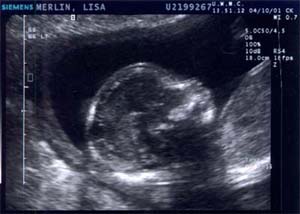

Baby B on 10 APRIL 2001 - Week 17

Baby B waving